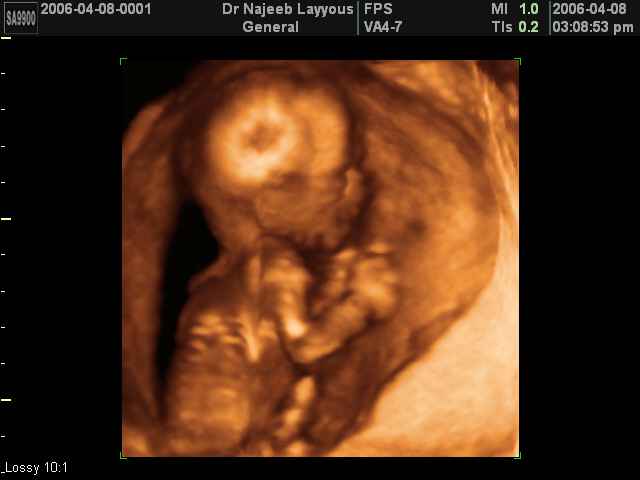

- Fetal Behavior Ultrasound Photos

Ultrasound Photos in 3D showing Fetal Behavior Inside the uterus | Dr N Layyous